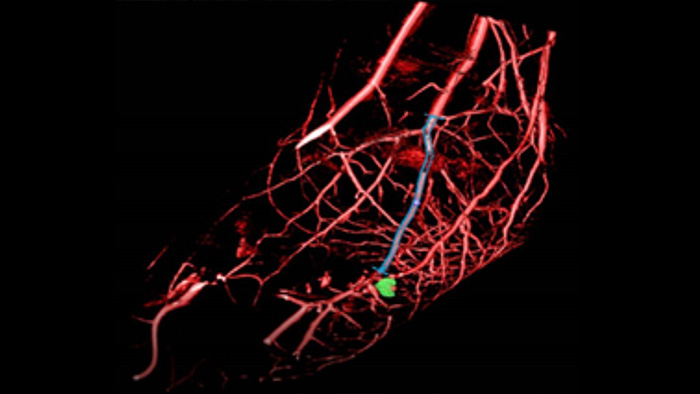

O SmartCT Roadmap facilita intervenções complexas fornecendo orientação de imagem 3D em tempo real que pode ser segmentada para enfatizar lesões e vasos alvo, auxiliando a navegação através de estruturas de vasos complexas. Tudo isto é controlado através do ecrã tátil na mesa.